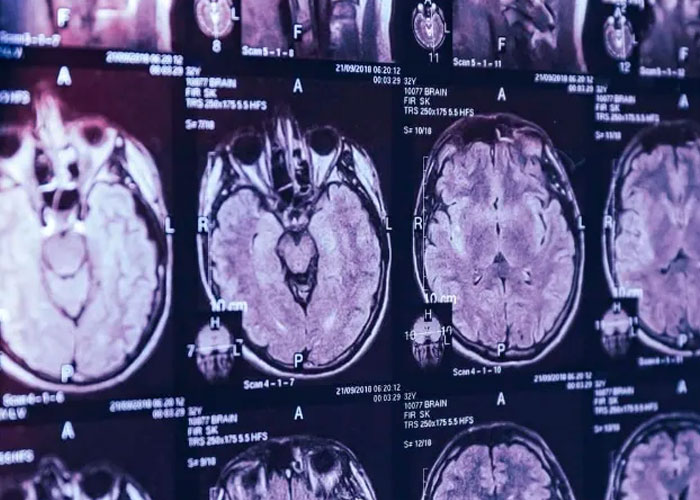

La Oficina del Director Médico de Salud de New Brunswick, en Canadá ha dicho públicamente que 48 personas de ambos sexos, de entre 18 y 85 años, han tenido la enfermedad; pero las fuentes le dijeron a The Guardian que se cree que este número es mucho mayor. Nueve personas han muerto a causa de la enfermedad, dijo la Oficina

Después de esta declaración, se presentó un documento a la Asociación Canadiense de Neuropatólogos; que indicaba que aquellos que murieron con la enfermedad fallecieron debido a diagnósticos incorrectos o perdidos. Estos como el Alzheimer y el cáncer, y no formaban parte del grupo.

El número de casos que están siendo investigados ha permanecido en 48 desde la primavera de 2021; pero múltiples fuentes aseguran que la cifra podría ya haber alcanzado los 150.